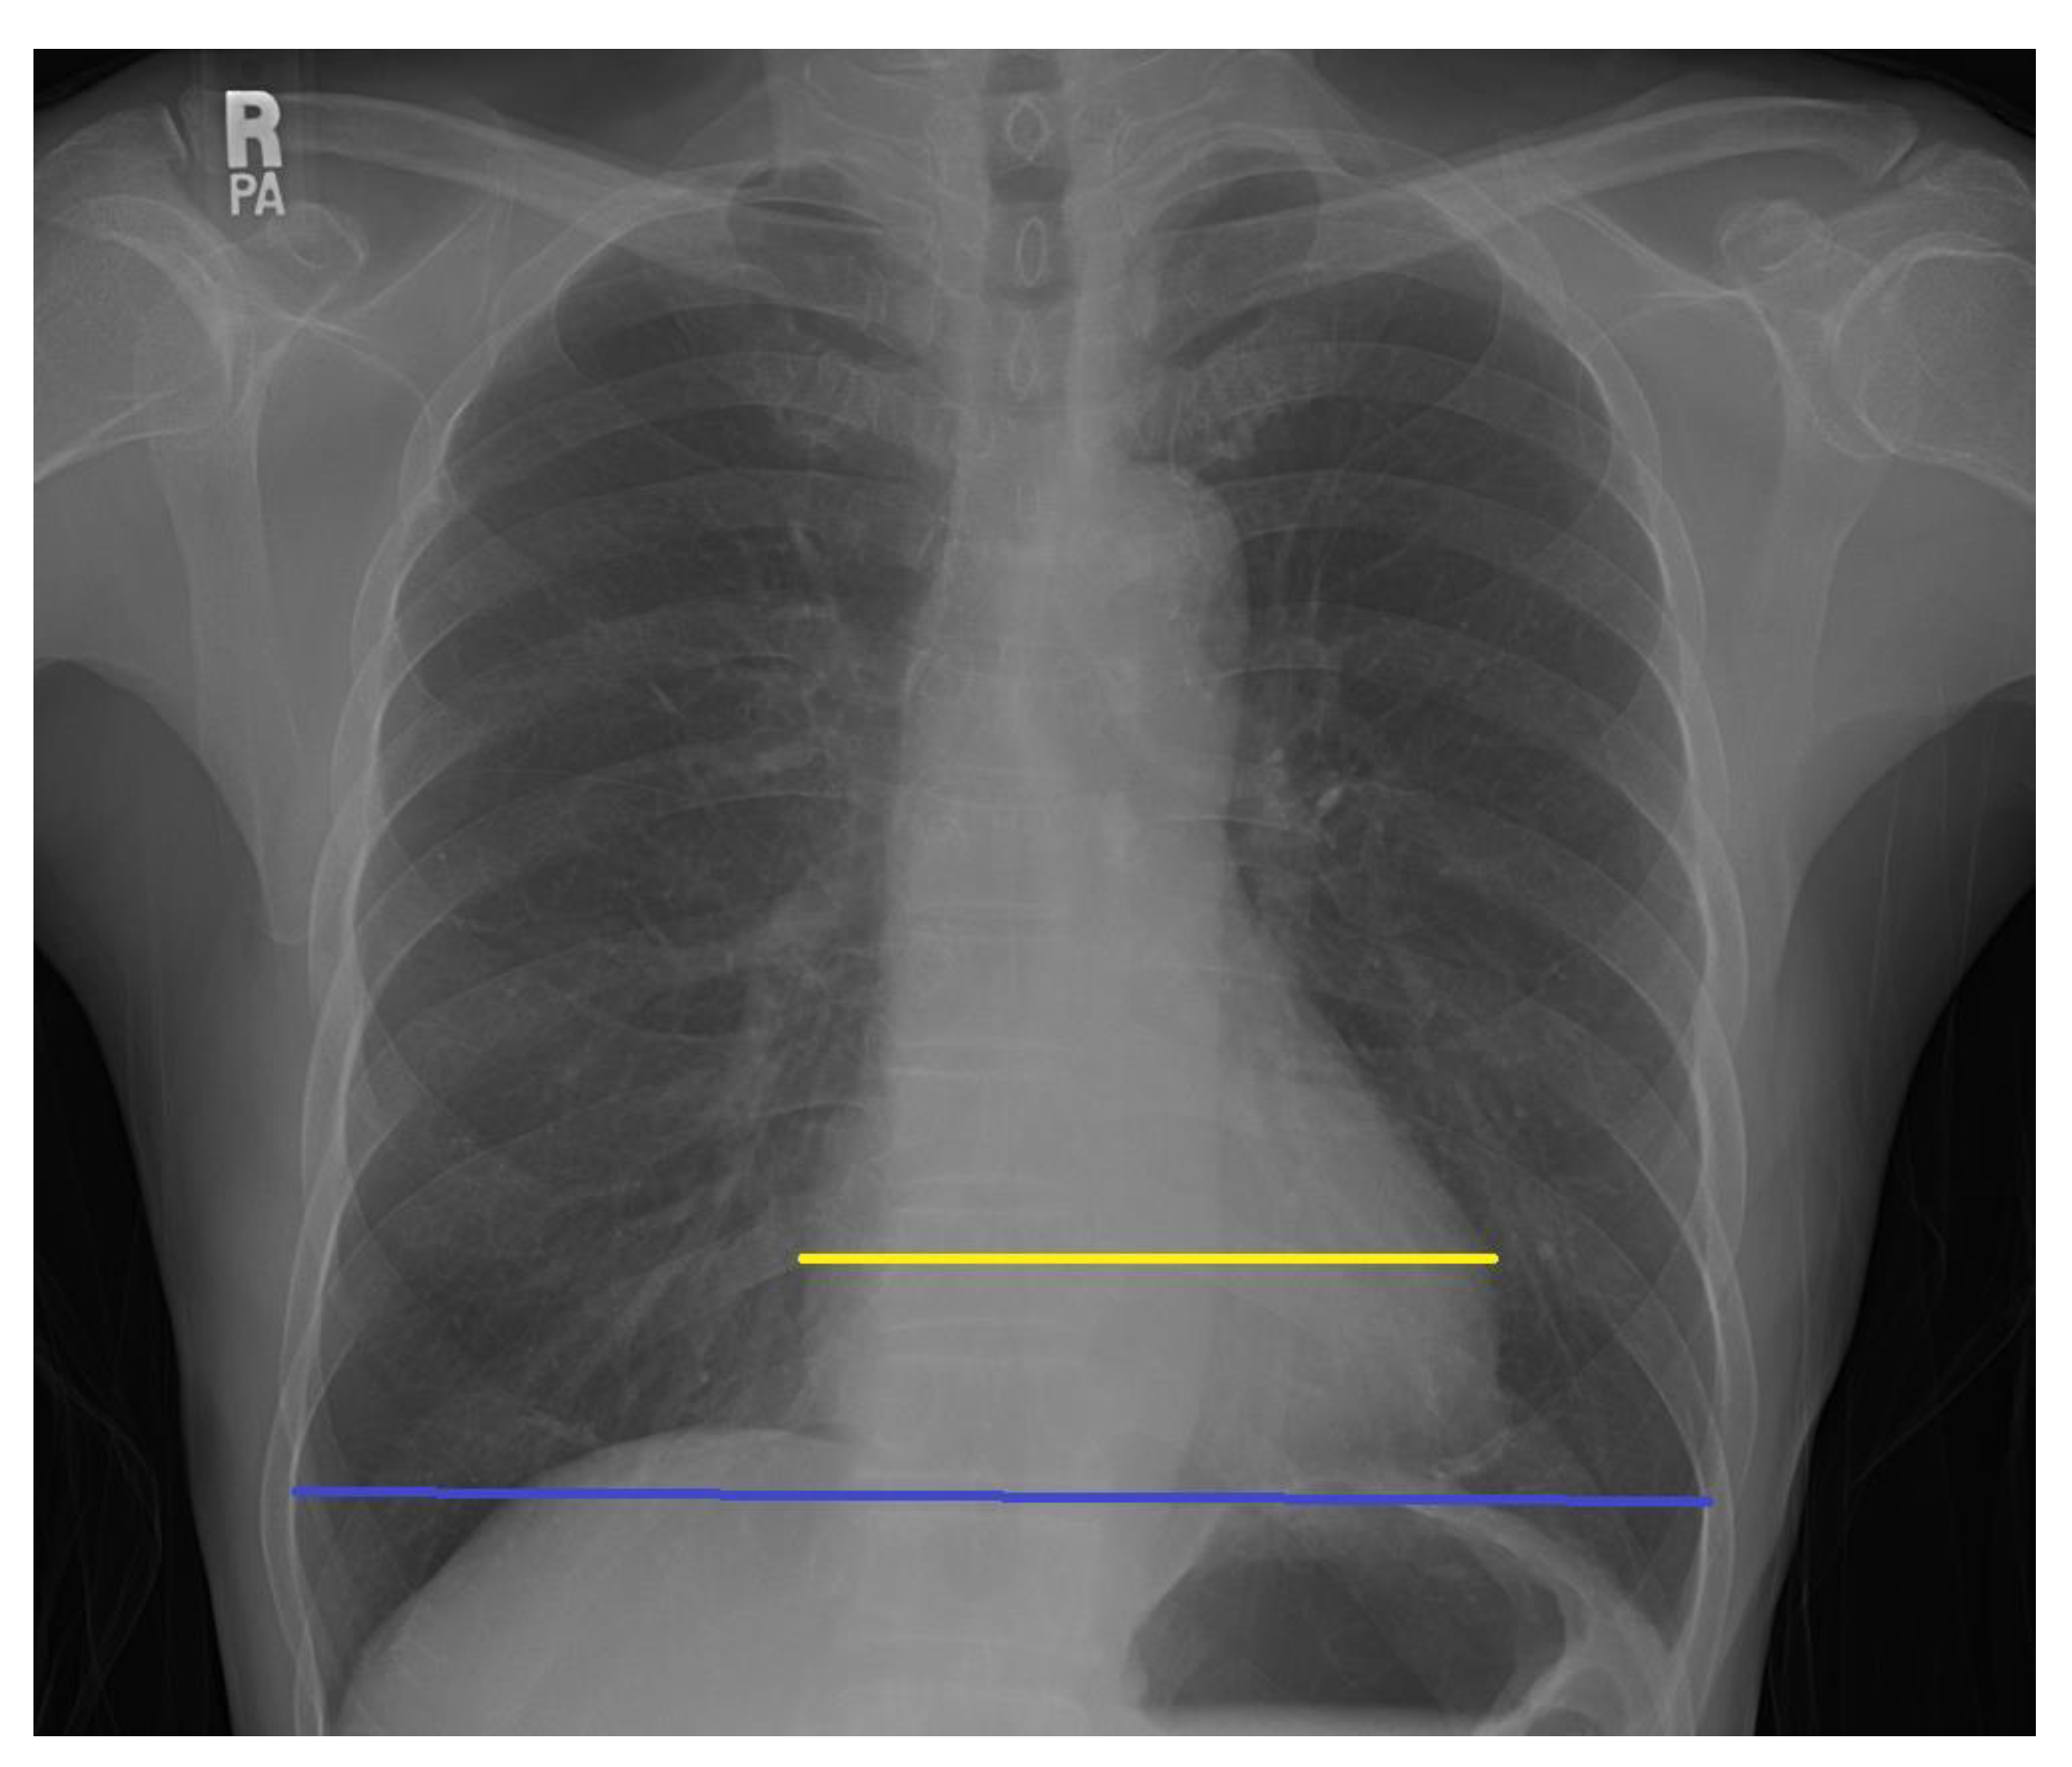

Clinical Assessment Of Cardiothoracic Ratio And Aortic Arch Download Scientific Diagram